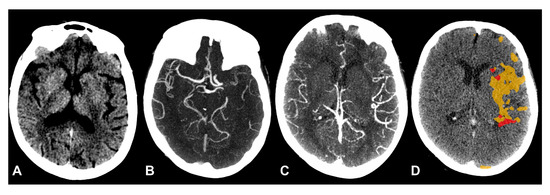

2.2. Image Acquisition and Processing

2.3. Imaging Analyses